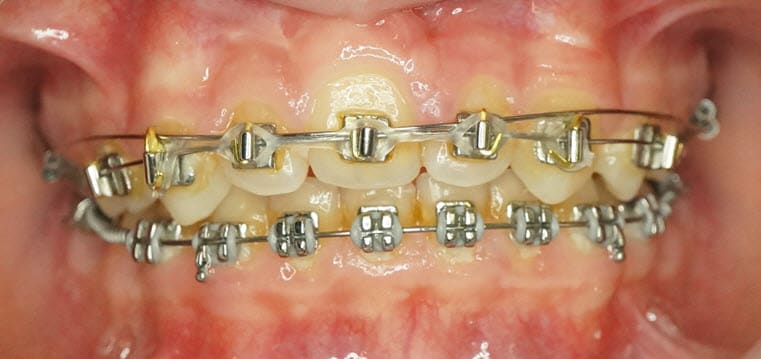

Cette fois elle a 10, on va démarrer quelque chose, mais quoi ?

On ouvre pour remplacer à terme la 21 ou est-ce qu'on ferme l'espace ?

Votre avis ?